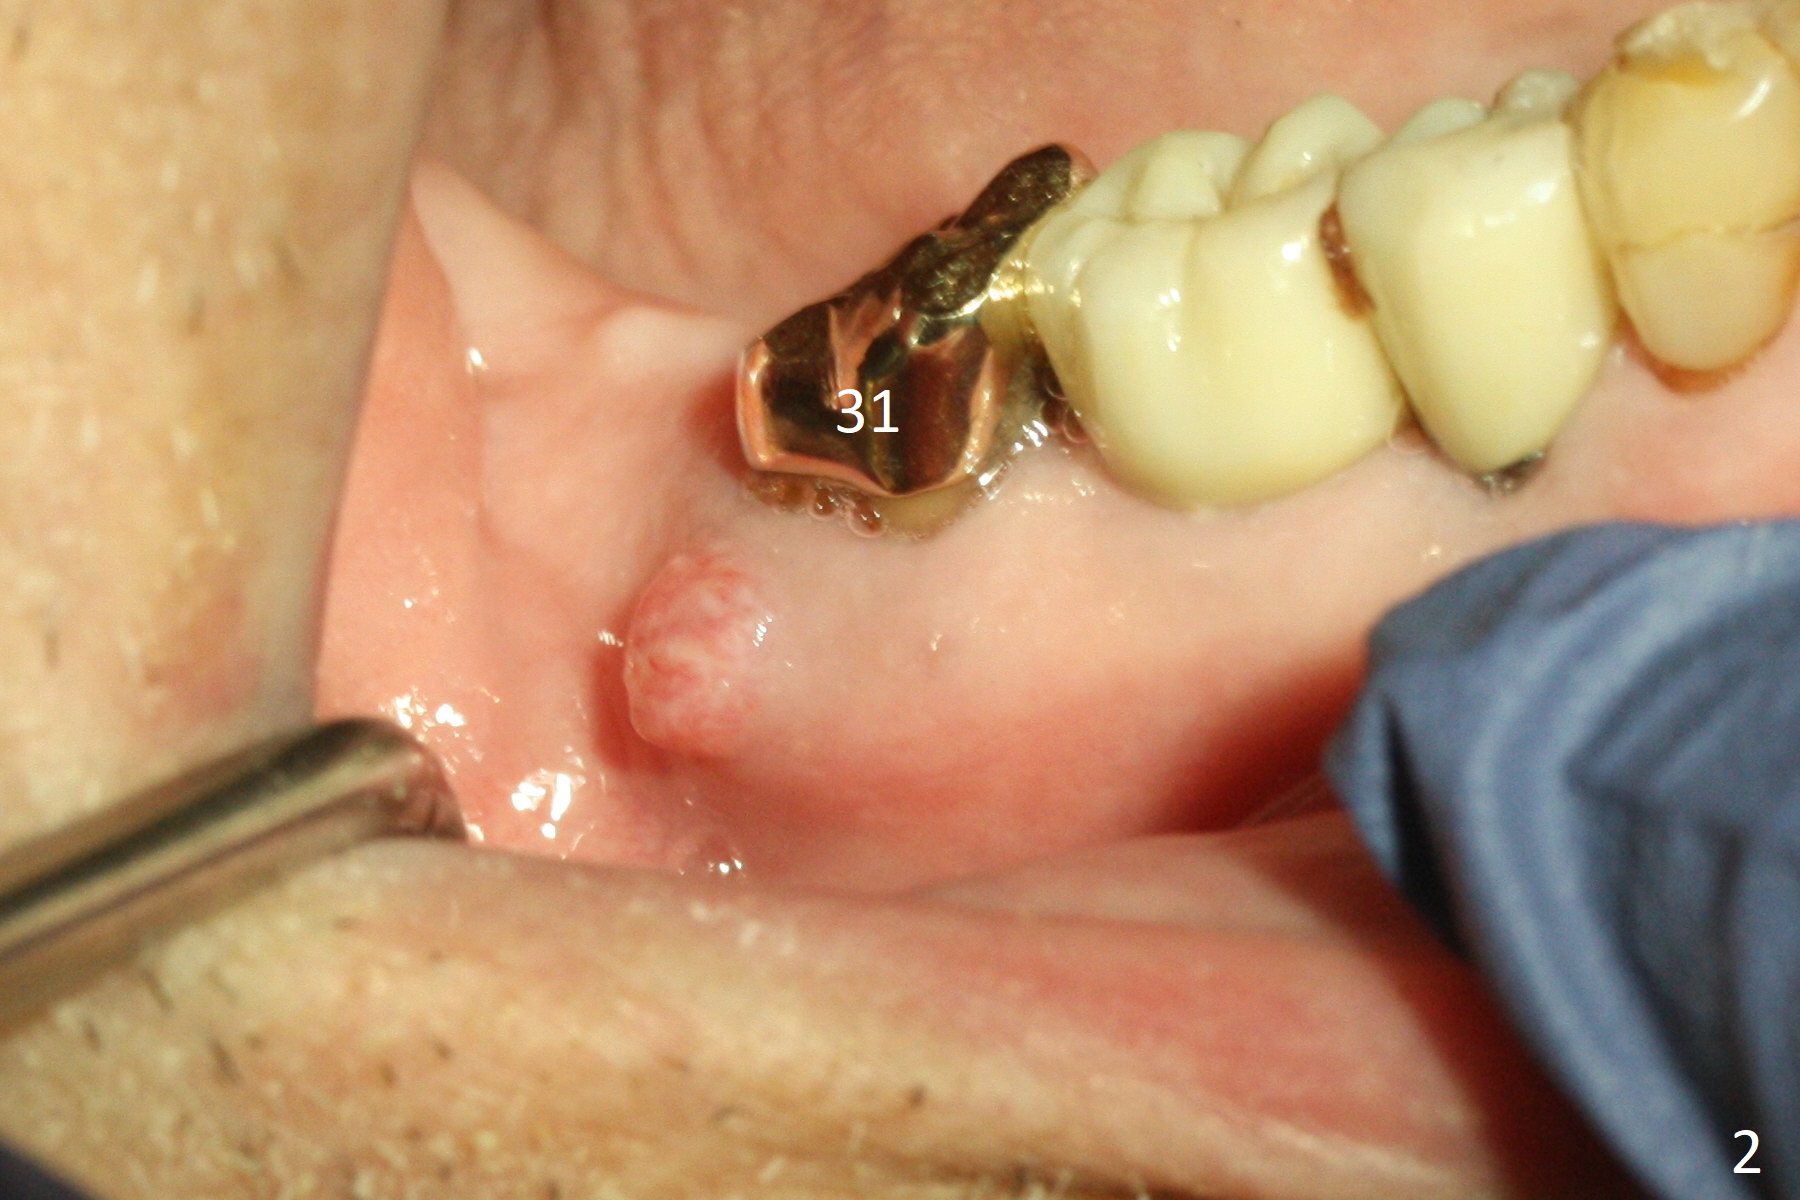

A 87-year-old man was asymptomatic with the tooth #31 eight months earlier (Fig.1), as compared to now (Fig.2). After extraction, osteotomy will be initiated in the septum (where there is more bone height) using IS 6 mm stopper (Fig.3 red line), followed by PA. If PA does not show the Inferior Alveolar Canal (Fig.1 red dashed line), take panoramic X-ray. A 5.5x13 mm implant will be placed (7 mm may not be covered by the native bone). The mesial root vertical root fracture is more obvious 7 months later (Fig.4,5).